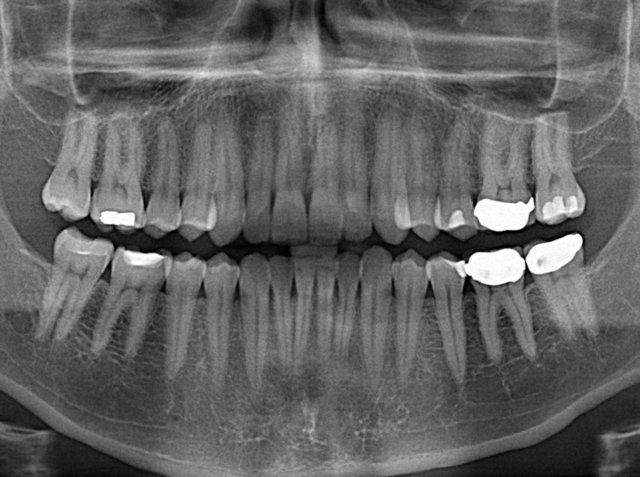

به گزارش ایسنا، دکتر جمشید کرمانچی با بیان اینکه یکی از دغدغههای بیماران خاص، دریافت خدمات دندانپزشکی است، گفت: نیاز بیماران خاص به خدمات دندانپزشکی به عنوان یک اولویت وزارت بهداشت، جزو سیاستهای کشوری است.

بنابر اعلام وبدا، وی گفت: نیاز بیماران خاص به خدمات دندانپزشکی به عنوان یک اولویت وزارت بهداشت، جزو سیاستهای کشوری است، زیرا یکی از دغدغههای بزرگ بیماران خاص، دریافت خدمات دندانپزشکی است که خیلی از مراکز ارائه نمیدهند.

کرمانچی تصریح کرد: این بیماران یک سری خدمات سرپایی نیاز دارند، مانند بهداشت دهان و دندان دورهای، خدمات پایه، خدمات ارتودنسی و خدمات تخصصی که برخی خدمات برای این گروه بیماران باید تحت بیهوشی باشد.